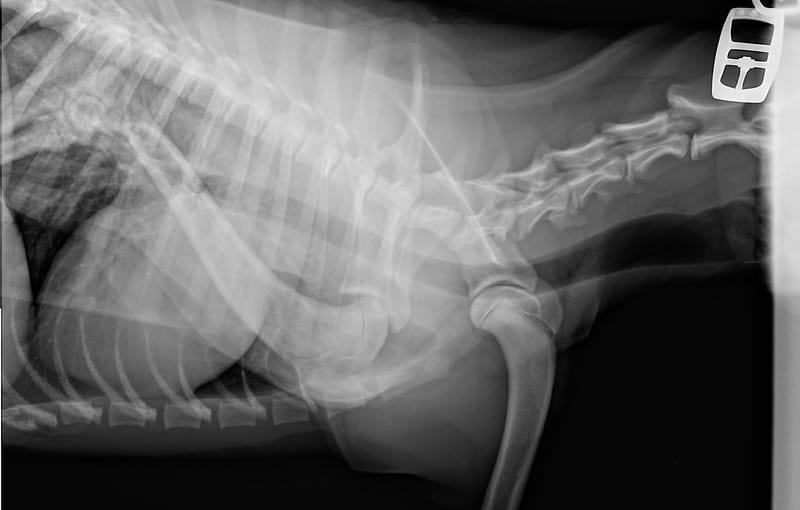

Joint Replacement in Dogs

Joint Replacement in Dogs Lab Dog Joints By following the tips and tricks discussed in this article, you can help prevent joint issues from occurring and ensure that your furry friend lives a long and active life. taking care of your labrador retriever’s joints is crucial for their overall health and happiness. lab hip dysplasia is a malformation of the hip joint where the head. Lab Dog Joints.